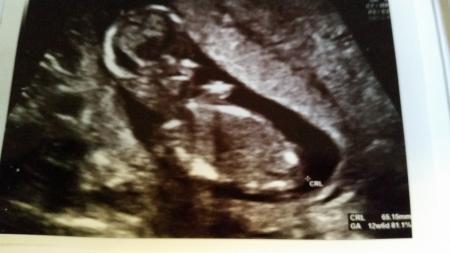

Hier die Bilder vom Ersttrimester Screening und vom letzten FA Besuch.

BIld Nr. 2

So jetzt habe ich alle hinzugefügt. Bild 1-3 sind vom Ersttrimesterscreening und die anderen von meiner Ärztin ... Schönen Abend noch Lg Rosi